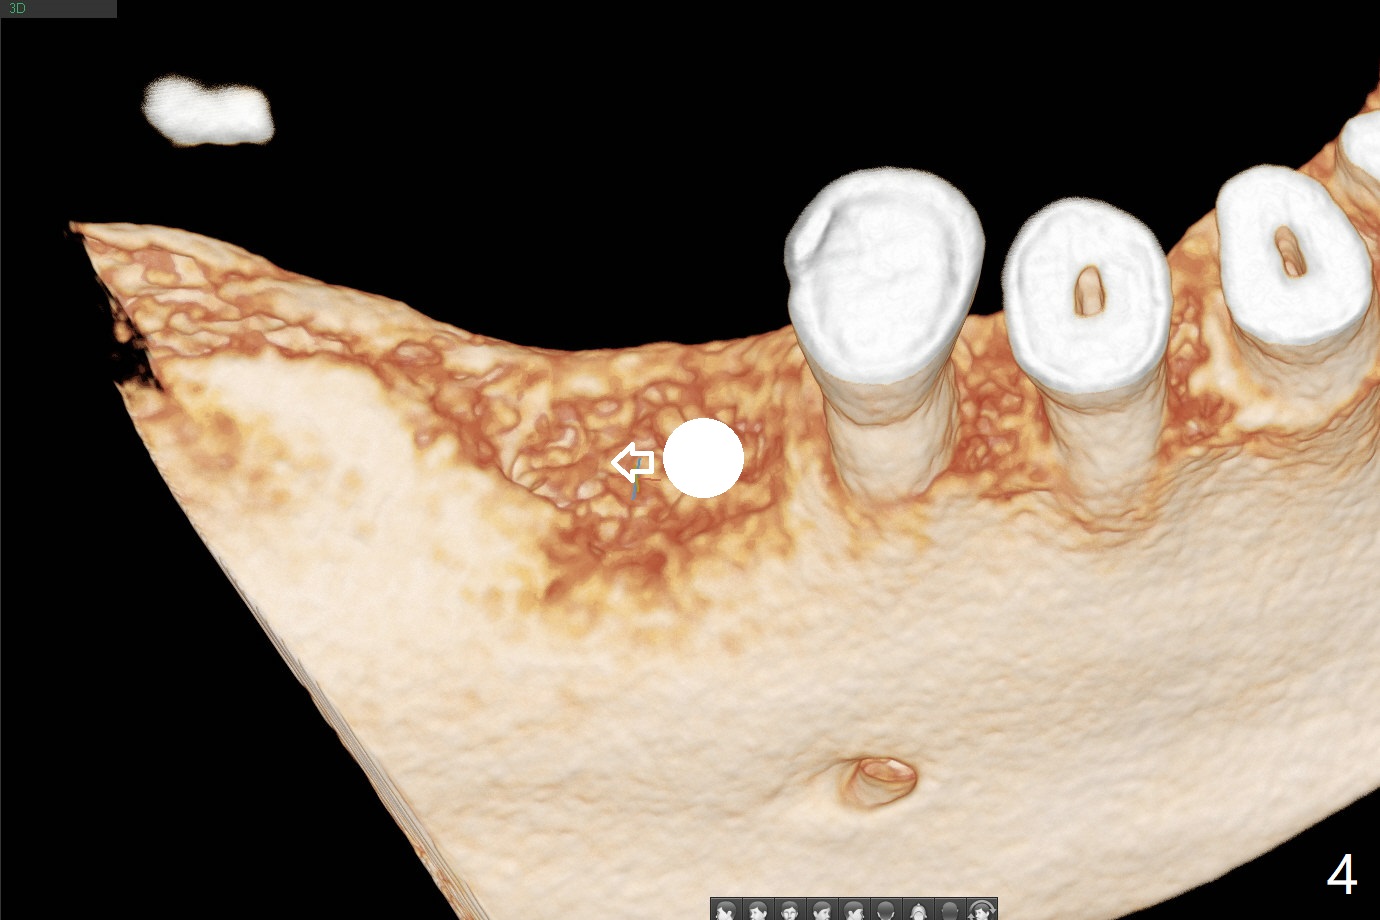

74岁女,右下6因植牙周围炎,植体取出,植骨,术后14个月回来做导板植牙术,局部infiltration时,发现位点中央有些分泌物,刮匙证实有一个瘘道(图一),翻瓣似乎不可避免,骨质缺损没有完全愈合(图二),其实仔细温习术前CT也能发现缺损(图三),导板钻洞位于缺损近中(图四:白圆圈),随着钻头直径增大,钻洞会偏移远中(图四:箭头)和颊侧(由于舌侧骨板厚,颊侧骨板低)。因此用过4毫米钻头后,植入4毫米报废IS植体,接近颊侧。同时为了防止植体断裂,选择五级钛植体(图五)。由于扭力低(手植入,有间隙:图五:<),包埋,使用自体骨和异体骨(皮质,*)。覆盖Osteogen tape后,PGA缝合,牙周胶水(图六)。如果植入4.5毫米植体,后者会更偏移远中。